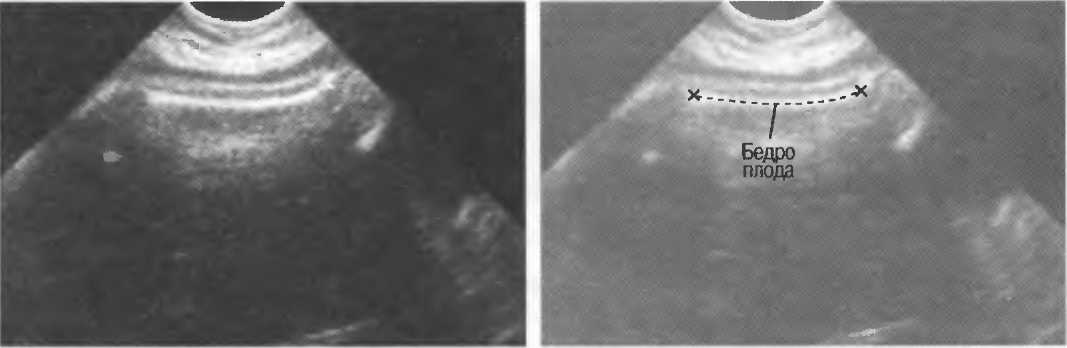

Неполное изображение

Артефакты в результате неполного изображения являются источником тревоги у исследователя, так как получается изображение только той части структуры, которая находится в плоскости сканирования. Так, при исследовании плода может визуализироваться только часть кости, а остальная часть может не попадать в плоскость. В результате, кость может выглядеть неполной или короче, чем она есть на самом деле (рис. 21а,б).

Рис.21а. Неполное изображение кости плода.

Рис.21б. В данном случае кость плода визуализируется полностью.